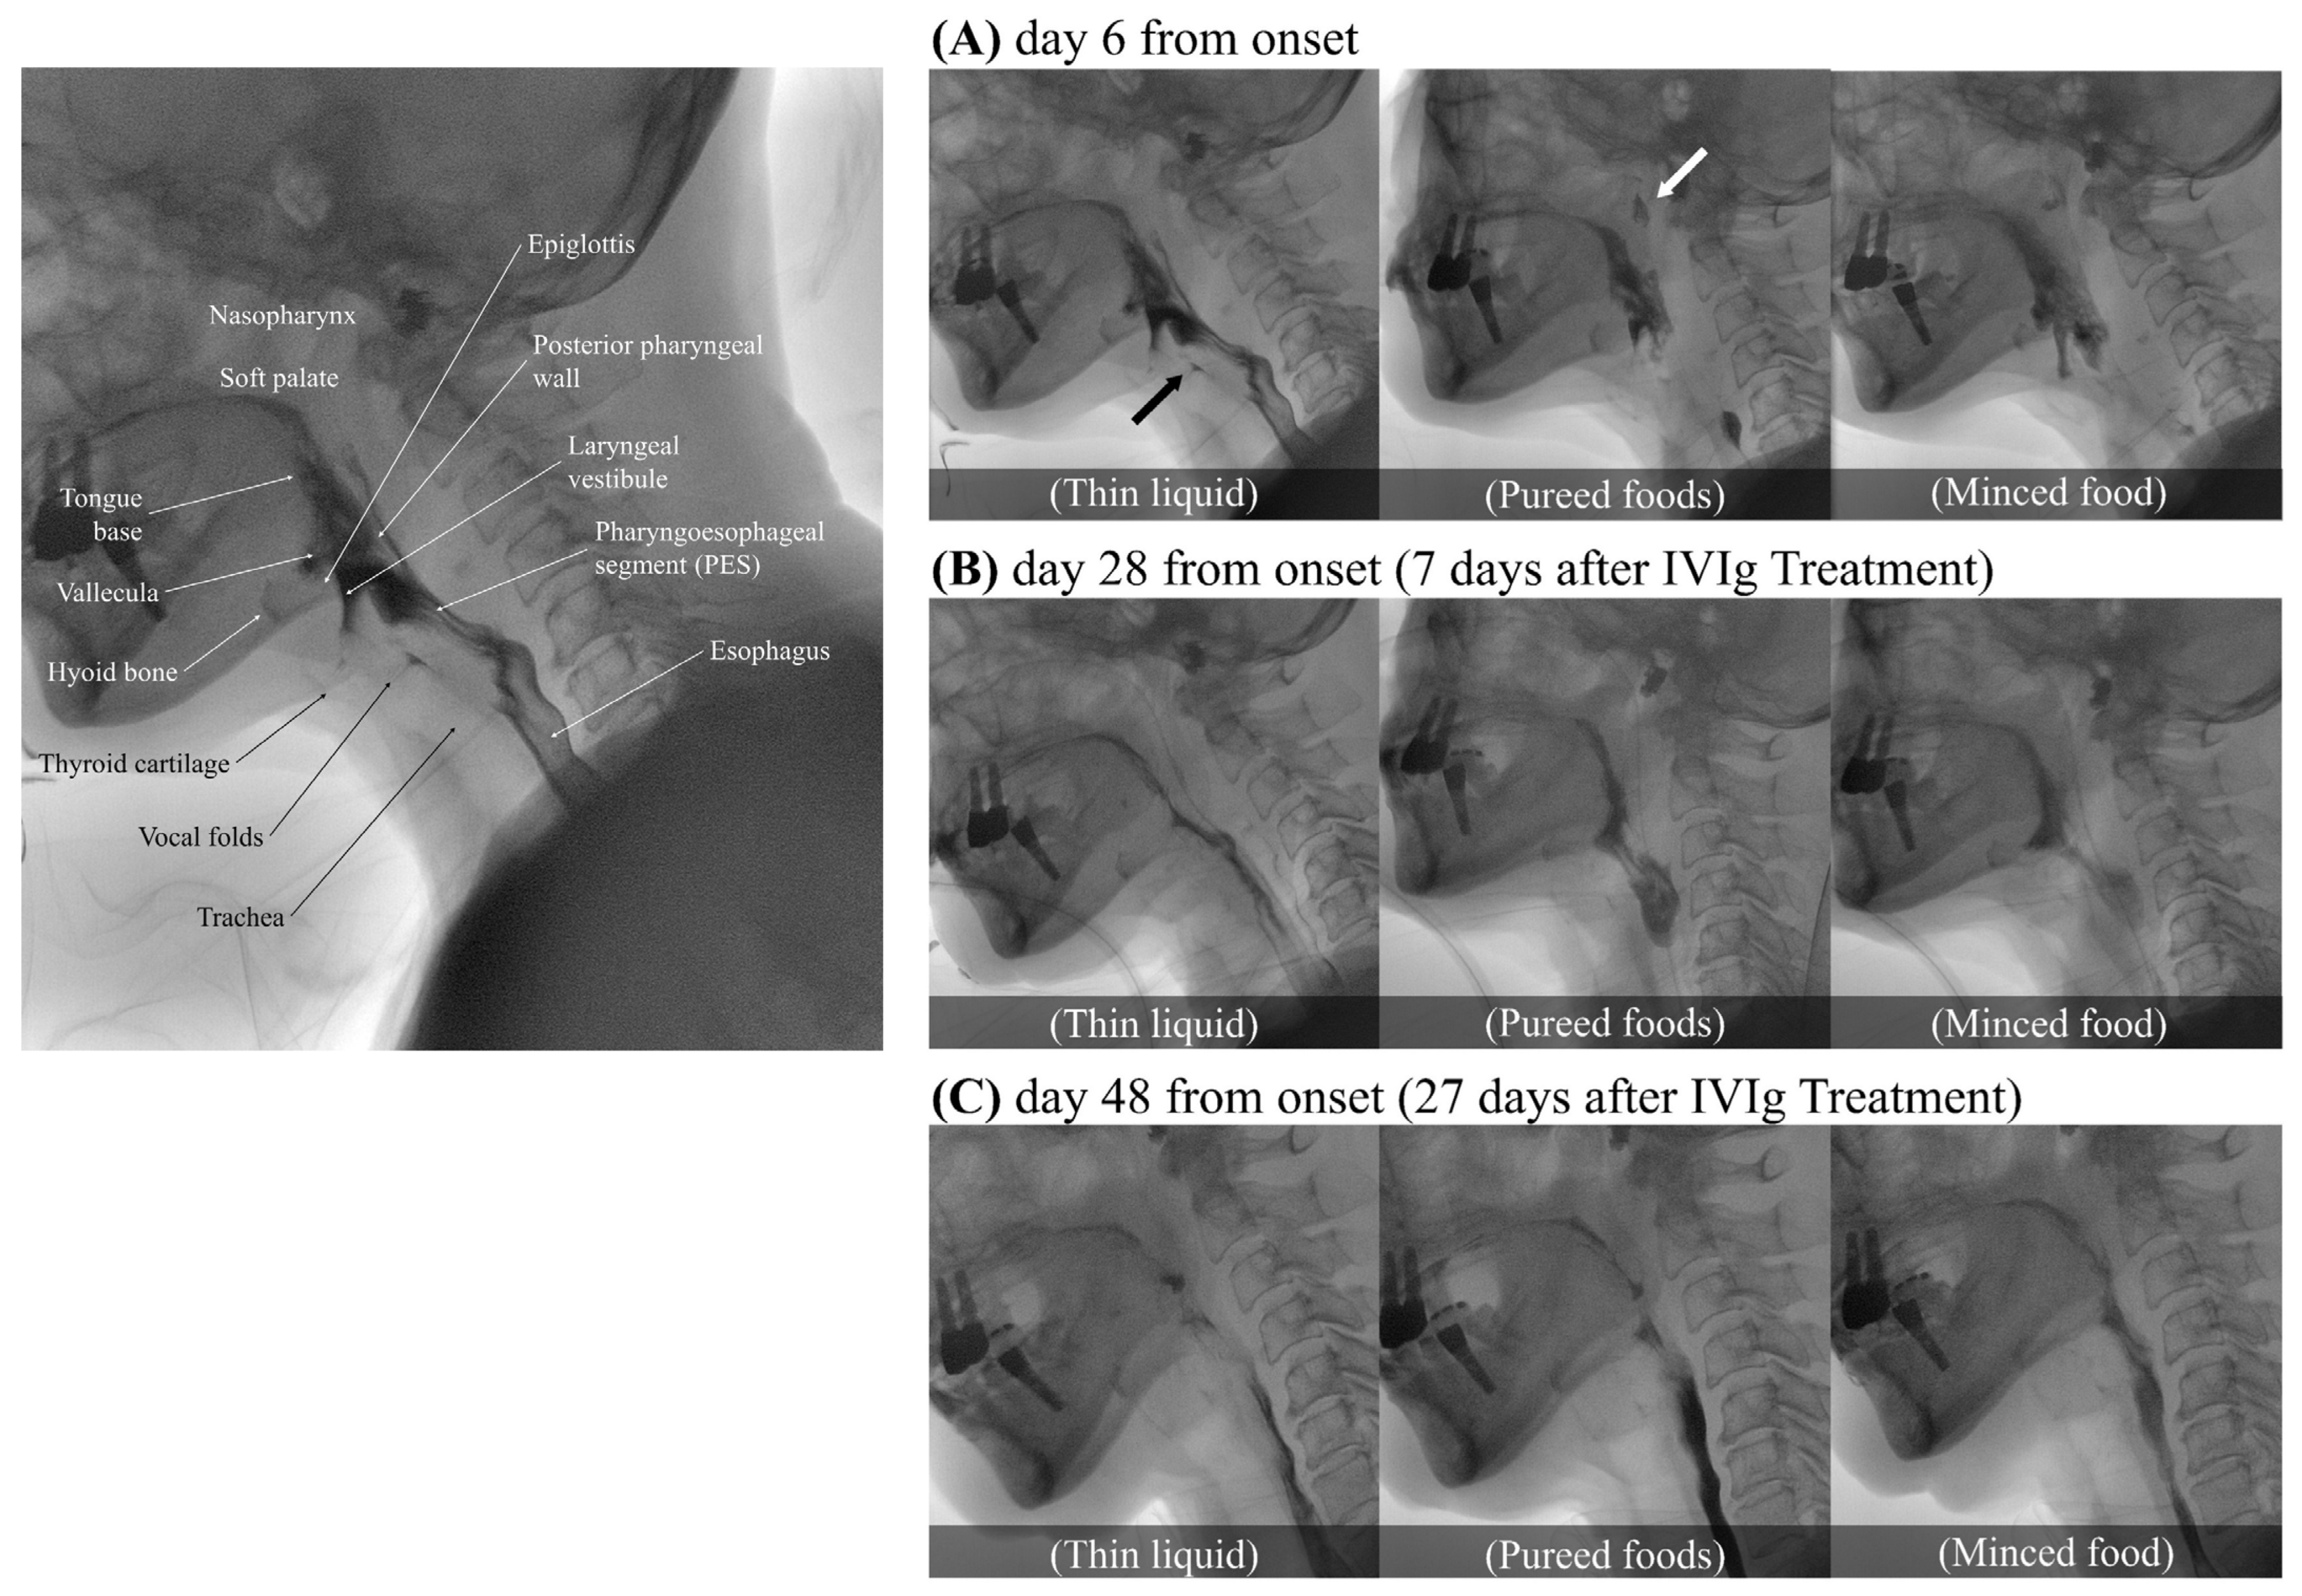

The video fluoroscopic swallowing study (VFSS) was conducted on day 6 of the illness (Figure 1A). To confirm the flow and textural characteristics of our testing material, we used the International Dysphagia Diet Standardization Initiative (IDDSI) method, which categorizes food materials into a continuum of eight levels (0–7). Her lip closure, tongue control, and mastication appeared intact during the examination. In the context of pureed foods (IDDSI level 4), a wide column of bolus was observed between the base of tongue and the posterior pharyngeal wall due to the decreased retraction of the tongue base. Minimal to no movement of the thyroid cartilage, hyoid bone, and epiglottis resulted in a wide column of contrast in the laryngeal vestibule and led to silent aspiration (PAS 8). Significant narrowing of the pharyngoesophageal segment (PES) caused minimal distention and lasted shortly, leading to marked obstruction. More than half of the food material remained within the pharyngeal structures due to decreased pharyngeal contraction. Little clearance was observed after multiple swallows. Due to decreased soft palate elevation, food material escaped to the level of nasopharynx. Silent aspiration in thin liquid without a coughing reflex was noted (IDDSI level 0, penetration/aspiration scale (PAS) 8). In the AP view, delayed vocal cord adduction was observed on the left side, and esophageal clearance appeared normal. As the symptoms progressed, follow-up VFSS was conducted on day 14. Compared to the previous examination, there were some findings that either remained similar or showed slight deterioration. Nasogastric tube feeding became necessary due to significant weight loss, with a 9 kg loss within a span of 2 weeks.

A cerebrospinal fluid (CSF) analysis performed on the 21st day of the illness revealed a mildly elevated total protein concentration (51 mg/dL), no white blood cells, and a normal glucose concentration (77 mg/dL), indicating albuminocytological dissociation. Following a thorough exclusion of alternative diagnoses, we consequently diagnosed the patient with an atypical variant of GBS, specifically involving cranial nerve (CN) X, and initiated intravenous immunoglobulin (IVIg) treatment for 5 days, from day 21 to day 25 of the illness. Following the initiation of IVIg treatment, the restoration of the gag reflex was observed on the third day of treatment. Significant clinical improvement was confirmed through VFSS a week after the initiation of IVIg (on day 28 from the onset), indicating a more definitive response to the therapy (Figure 1B). Soft palate elevation and tongue base retraction showed partial improvement, with a trace of contrast observed in the space between the soft palate/the base of tongue and the pharyngeal wall. Full superior movement of the thyroid cartilage and partial anterior movement of hyoid bone were observed. Additionally, with fully recovered superior movement of the thyroid cartilage and partially improved movement of the hyoid bone and epiglottis, no air or contrast was noted in the laryngeal vestibule. Minimal penetration (PAS 3) was observed across all evaluated diets, including thick pureed foods (IDDSI level 4), minced food (IDDSI level 5), soft bite-sized food (IDDSI level 6), and thin liquid (IDDSI level 0). The PES opening and pharyngeal contraction also exhibited a partial improvement, allowing a greater amount of food to pass through the esophagus with a double swallow. In the AP view, normal recovery of vocal cord adduction was observed. Consequently, the patient no longer required a nasogastric tube and began consuming pureed foods, although still experiencing difficulty with solid foods. In the VFSS conducted on day 48 of the illness, 27 days after the initiation of IVIg treatment (Figure 1C), it was confirmed that her swallowing function had fully recovered to normal, enabling her to safely consume any food without restriction.

Figure 1. Serial Video Fluoroscopic Swallowing Study (VFSS) images of the patient on days 6, 28, and 48 from the onset of the illness, utilizing thin liquid (International Dysphagia Diet Standardization Initiative [IDDSI] level 0), pureed food (IDDSI level 4), and minced food (IDDSI level 5). All images were captured at the height of the swallow. The leftmost image depicts the oropharyngeal anatomy associated with the swallowing process. Part (A) shows silent aspiration (black arrow) and the escape of food material into the nasopharynx (white arrow). Part (B) shows partial improvement in soft palate elevation, epiglottis movement, tongue base retraction, and pharyngeal contraction. Minimal penetration is observed with all tested diets. Part (C) demonstrates complete recovery of swallowing function, returning to a normal state.